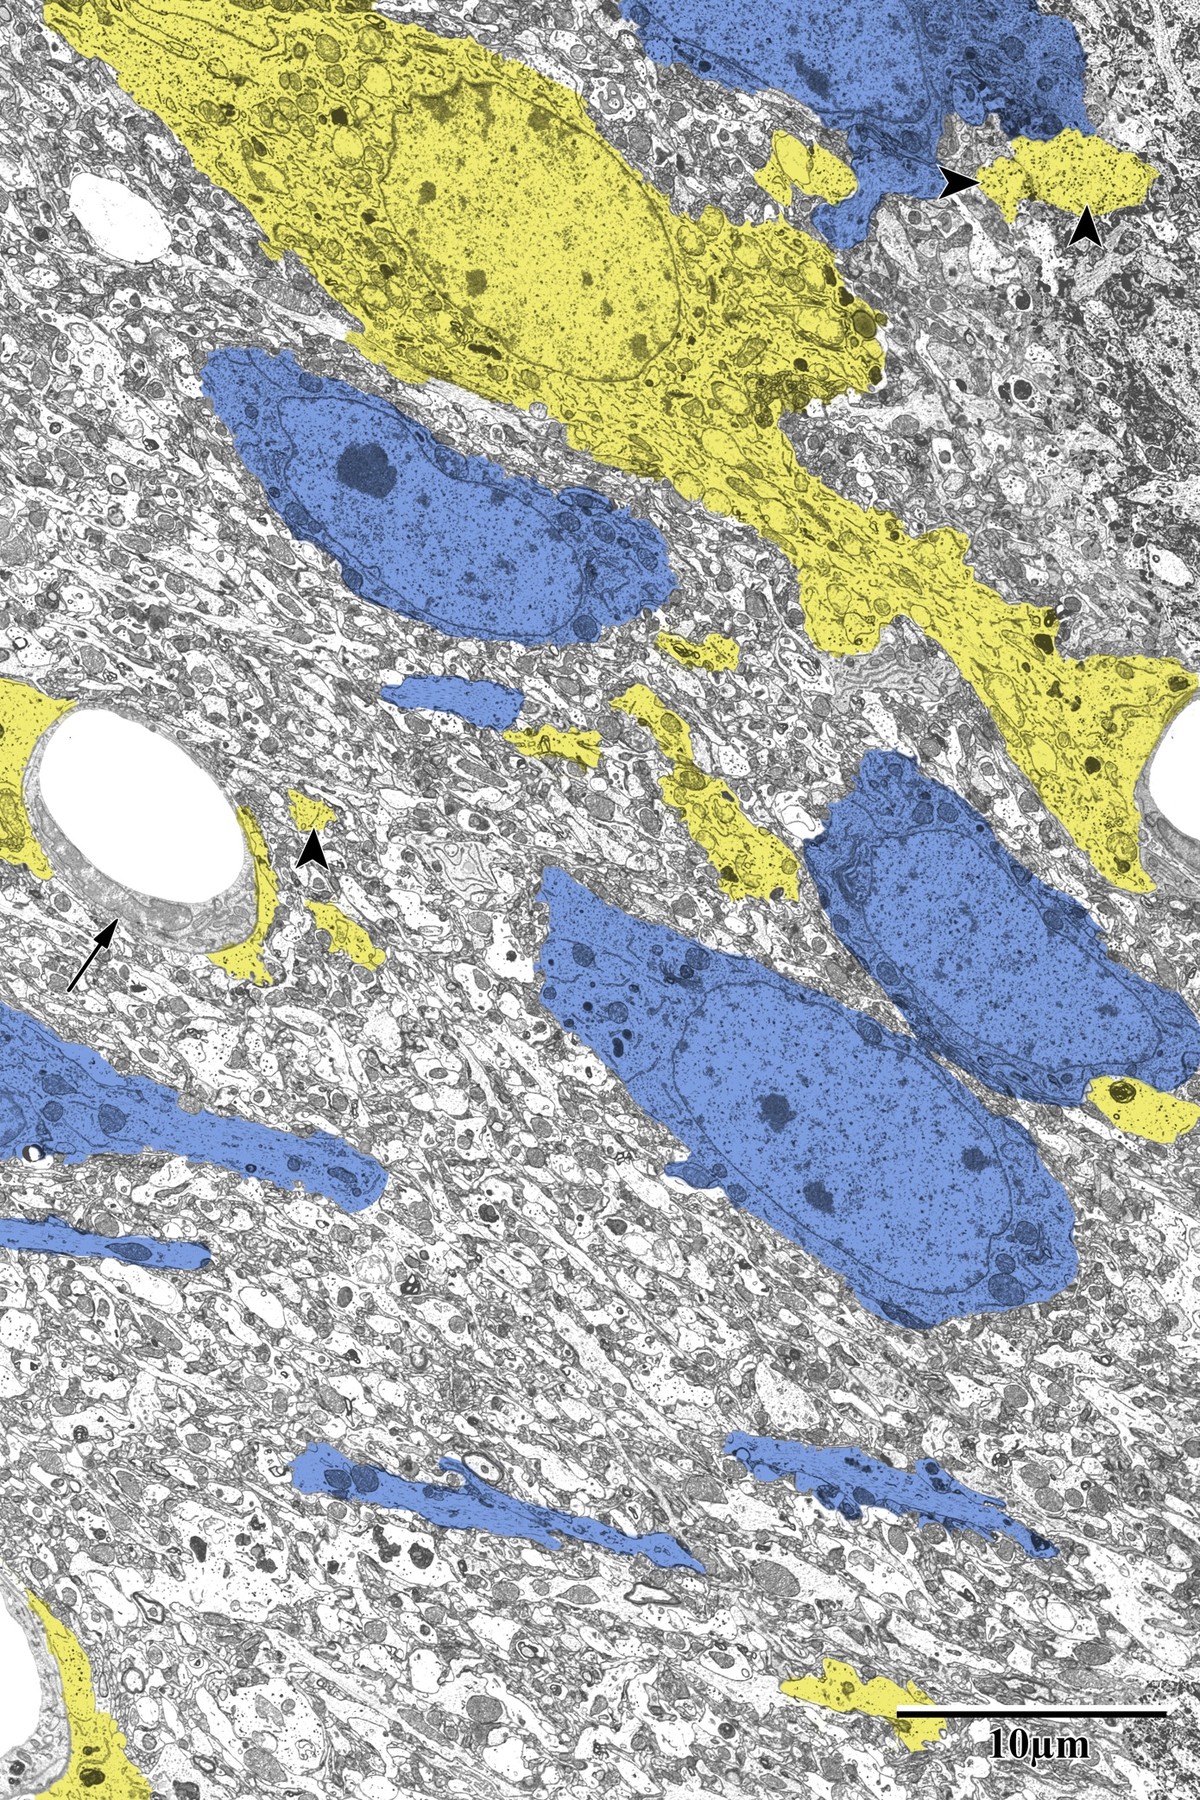

Astrocytes responded dramatically to ischemic injury, showing increased process area and reactive morphology in the peri-infarct zone. Astrocytic processes were traced and pseudocolored yellow for quantification, revealing glycogen granule accumulation, swollen mitochondria, and extensive perivascular endfeet coverage around capillaries.

Reactive Astrocytosis

Pseudocolored astrocytes (yellow) surrounding neurons (blue) in peri-infarct zone

Peri-infarct zone: reactive astrocytes (yellow) surrounding pyramidal neurons (blue). Note the dramatically increased astrocytic coverage compared to control tissue, with microglia also visible. From Bayati, BSc Honours Thesis 2018.